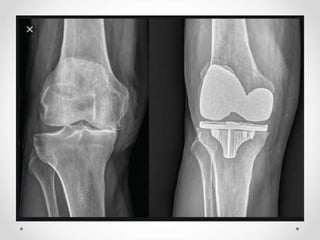

Pencitraan radiologis sinar-x osteoarthritis pada lutut

Gambaran radiologis anteroposterior lutut menunjukkan penyempitan

ruang sendi, sklerosis, dan pembentukan osteofit (panah)

Sumber : Jacobson, JA, et al. 2008. Radiographic Evaluation of Arthritis : Degenerative Joint Disease and Variation. Radiology. 248(3) : 737-747.

Pencitraan radiologis sinar-xosteoarthritis pada lutut Gambaran radiologis anteroposterior lutut menunjukkan penyempitan ruang sendi, sklerosis, dan pembentukan osteofit (panah) Sumber : Jacobson, JA, et al. 2008. Radiographic Evaluation of Arthritis : Degenerative Joint Disease and Variation. Radiology. 248(3) : 737-747.